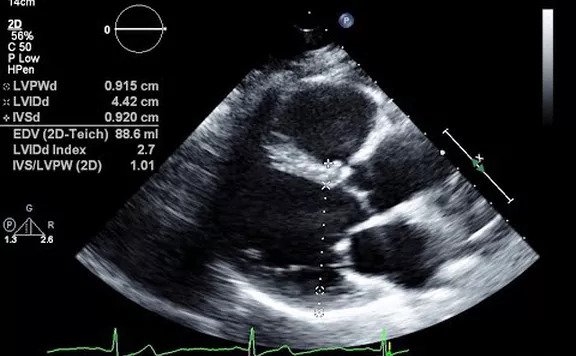

An echocardiography, echocardiogram, cardiac echo or simply an echo, is an ultrasound of the heart.

Echocardiography uses standard two-dimensional, three-dimensional, and Doppler ultrasound to create images of the heart.

Echocardiography has become routinely used in the diagnosis, management, and follow-up of patients with any suspected or known heart diseases. It is one of the most widely used diagnostic tests in cardiology. It can provide a wealth of helpful information, including the size and shape of the heart (internal chamber size quantification), pumping capacity, and the location and extent of any tissue damage. An echocardiogram can also give physicians other estimates of heart function, such as a calculation of the cardiac output, ejection fraction, and diastolic function (how well the heart relaxes).

Echocardiography is an important tool in assessing wall motion abnormality in patients with suspected cardiac disease. It is a tool which helps in reaching an early diagnosis of myocardial infarction showing regional wall motion abnormality of the heart. Also, it is important in treatment and followup in patients with heart failure, by assessing ejection fraction.

Echocardiography can help detect cardiomyopathies, such as hypertrophic cardiomyopathy, dilated cardiomyopathy, and many others. The use of stress echocardiography may also help determine whether any chest pain or associated symptoms are related to heart disease. The biggest advantage to echocardiography is that it is not invasive (does not involve breaking the skin or entering body cavities) and has no known risks or side effects.

Not only can an echocardiogram create ultrasound images of heart structures, but it can also produce accurate assessment of the blood flowing through the heart by Doppler echocardiography, using pulsed- or continuous-wave Doppler ultrasound. This allows assessment of both normal and abnormal blood flow through the heart. Color Doppler, as well as spectral Doppler, is used to visualize any abnormal communications between the left and right sides of the heart, any leaking of blood through the valves (valvular regurgitation), and estimate how well the valves open (or do not open in the case of valvular stenosis). The Doppler technique can also be used for tissue motion and velocity measurement, by tissue Doppler echocardiography.